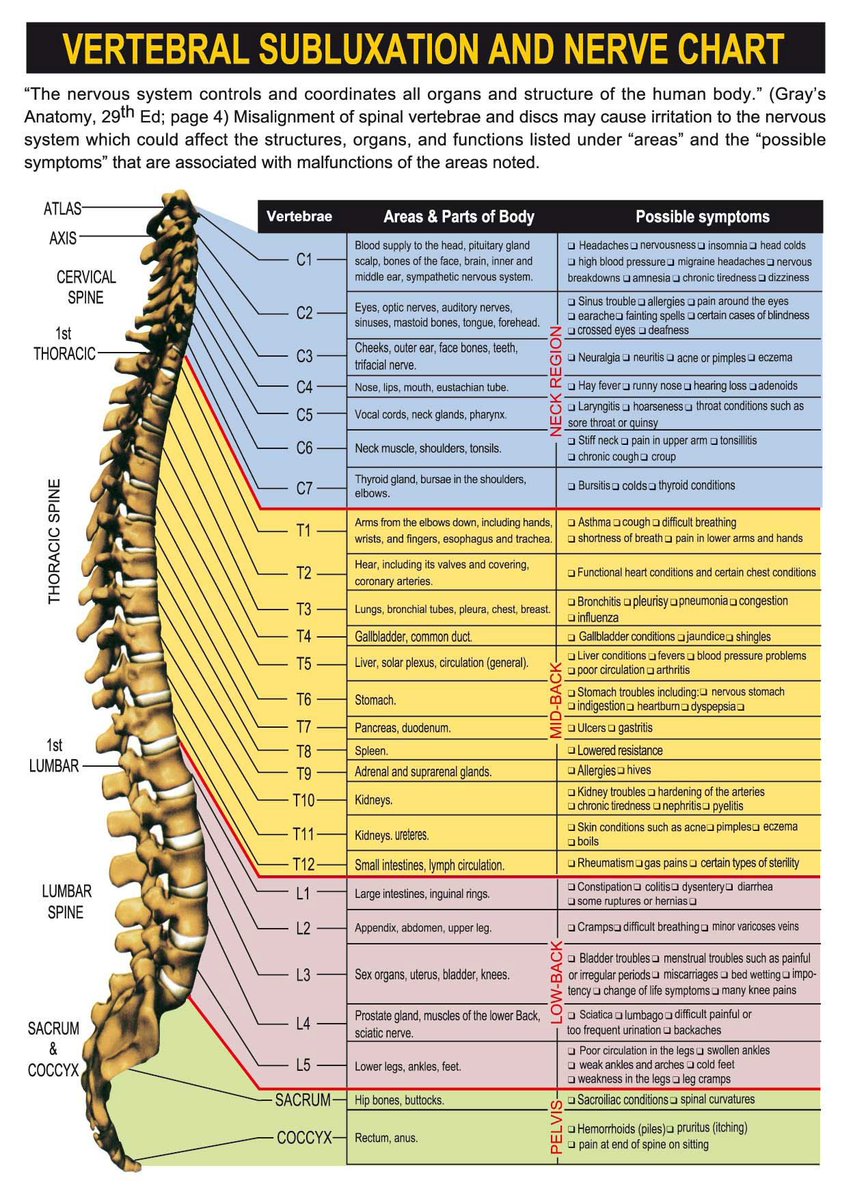

Misalignment of the #spinalvertebrae and #spinaldisc may cause irritation to the nervous system which could affect the structures, organs and functions listed under Areas and Possible symptoms. #spinalhealth #nervoussystem #vertebralcolumn